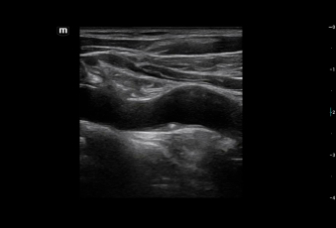

Consona presenta soluzioni nuove e concrete, che aiutano a effettuare diagnosi efficaci con semplicitĂ , rivolgendosi a un'ampia platea di pazienti. La serie mette a disposizione strumenti estremamente avanzati per rimanere all'avanguardia nella diagnosi cardiovascolare.

Galleria di immagini